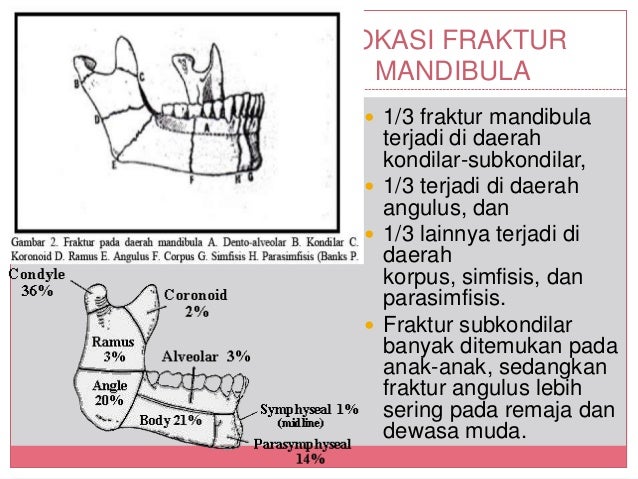

Hence, maxillofacial surgeons should be familiar with epidemiology of mandibular condylar fracture. Demography of the patients, causation, and characteristics of the fracture depends on various socio-economic factors. Mandibular condylar fracture is one of the commonest maxillofacial fractures treated by maxillofacial surgeons. Thapa, Swosti Wang, Jun Hu, Hong-Tao Zhang, Fu-Gui Ji, Ping Statistical difference was observed between these 2 groups (P condyle fractures should be treated by surgical reduction with the maintenance of the attachment of lateral pterygoid muscle, which is beneficial to repositioning the dislocated condyle to its original physiological position, to closure of the mandibular lingual gap, to restore the mandibular width.Įpidemiology of Surgically Managed Mandibular Condylar Fractures at a Tertiary Referral Hospital in Urban Southwest China. Seventeen of 22 condyle fractures were repositioned in the surgery group, whereas 4 of 22 condyle fractures were repositioned in the close treatment group. The surgical effect between these 2 groups was compared based on clinical examination and radiographic examination results.

Twenty-two sites were treated by open reduction, and all the medial condylar fragments were fixed with titanium screws whereas the other 22 sites underwent close treatment. Twenty-eight patients with MSF&DICF were included in this study. To evaluate the treatment methods of mandibular symphyseal fracture combined with dislocated intracapsular condylar fractures (MSF&DICF) and to compare the effect of different treatment methods of condylar fractures.